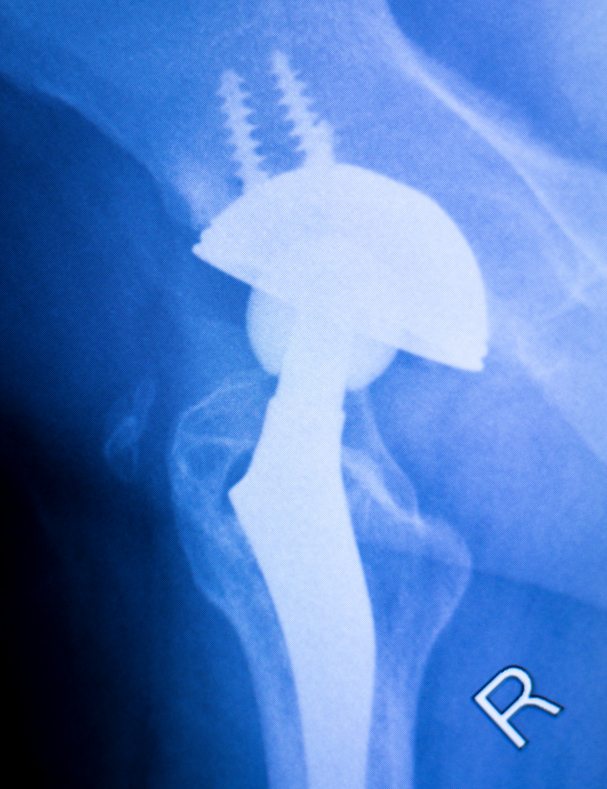

Total joint replacement is a surgical procedure in which parts of an arthritic or damaged joint are removed and replaced with a metal, plastic or ceramic device called a prosthesis. The prosthesis is designed to replicate the movement of a normal, healthy joint.

Technology is evolving: Joint replacement surgery is often the remedy for people to come back to an active and productive life. The present day joint replacement surgery is more advanced with better understanding of human anatomy based on improved imaging techniques.  Refined surgical techniques and technological advancement in the accuracy and design of implants help ensure complete and painless mobility. Computer aided navigation, patient-specific knee replacement and robotic knee replacement…all these factors and more have made this surgical procedure not only a reality, but a life changing experience.